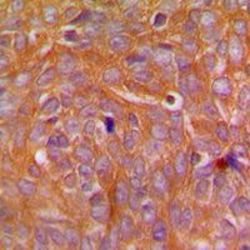

Supportive validation

- Submitted by

- GeneTex (provider)

- Main image

- Experimental details

- Immunohistochemical analysis of CARD14 staining in human breast cancer formalin fixed paraffin embedded tissue section. The section was pre-treated using heat mediated antigen retrieval with sodium citrate buffer (pH 6.0). The section was then incubated with the antibody at room temperature and detected using an HRP conjugated compact polymer system. DAB was used as the chromogen. The section was then counterstained with haematoxylin and mounted with DPX.